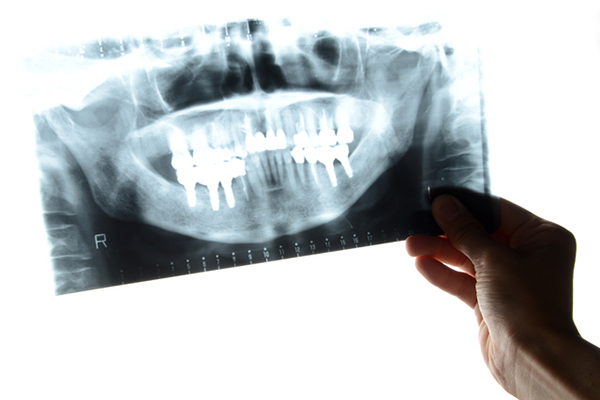

インプラントとは、歯の失った所に「第二の永久歯」として人工的に作られた歯根と人工歯を埋め込む画期的な治療法です。

人工歯根にあたるインプラントは、チタンと呼ばれる金属でできており、生体親和性に優れいているので、拒絶反応がなく顎の骨と結合します。